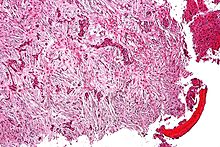

| Micrograph (using H&E stain) of an adamantinoma showing the biphasic histomorphology. | |

Histologically, islands of epithelial cells are found in a fibrous stroma. The tumor is typically well-demarcated, osteolytic and eccentric, with cystic zones resembling soap bubbles.[2]